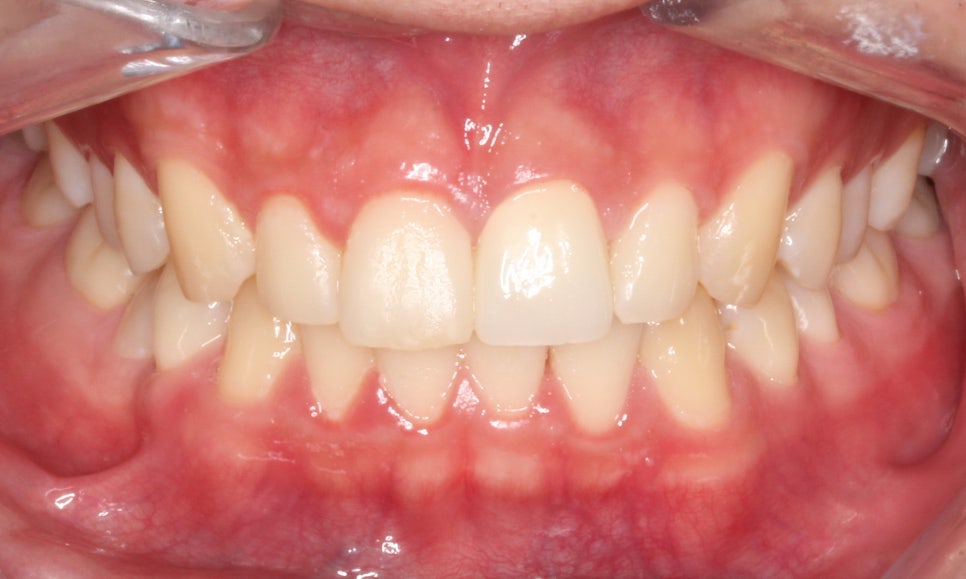

□ 깨진 앞니

출처:투디 치과/ 깨진 앞니 사례의 블링스 전후 사진입니다.